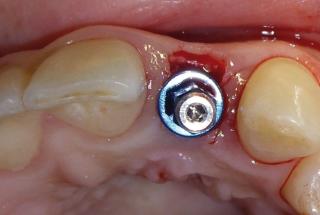

Clinical cases

MPI closely monitors clinical cases in the market to ensure their correct functioning and successful outcome.